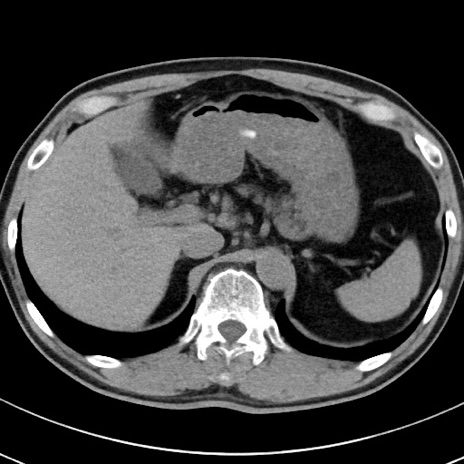

【腹部TIPS】症例29 参考症例 CT(横断像)

症例

70歳代男性